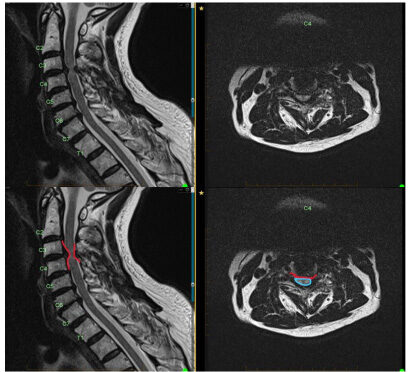

MRI of cervical disk herniation and compression. The compression is outlined in red on the bottom left image and the disk herniation causing compression is outlined in red on the right image with the spinal cord compression outlined in blue.